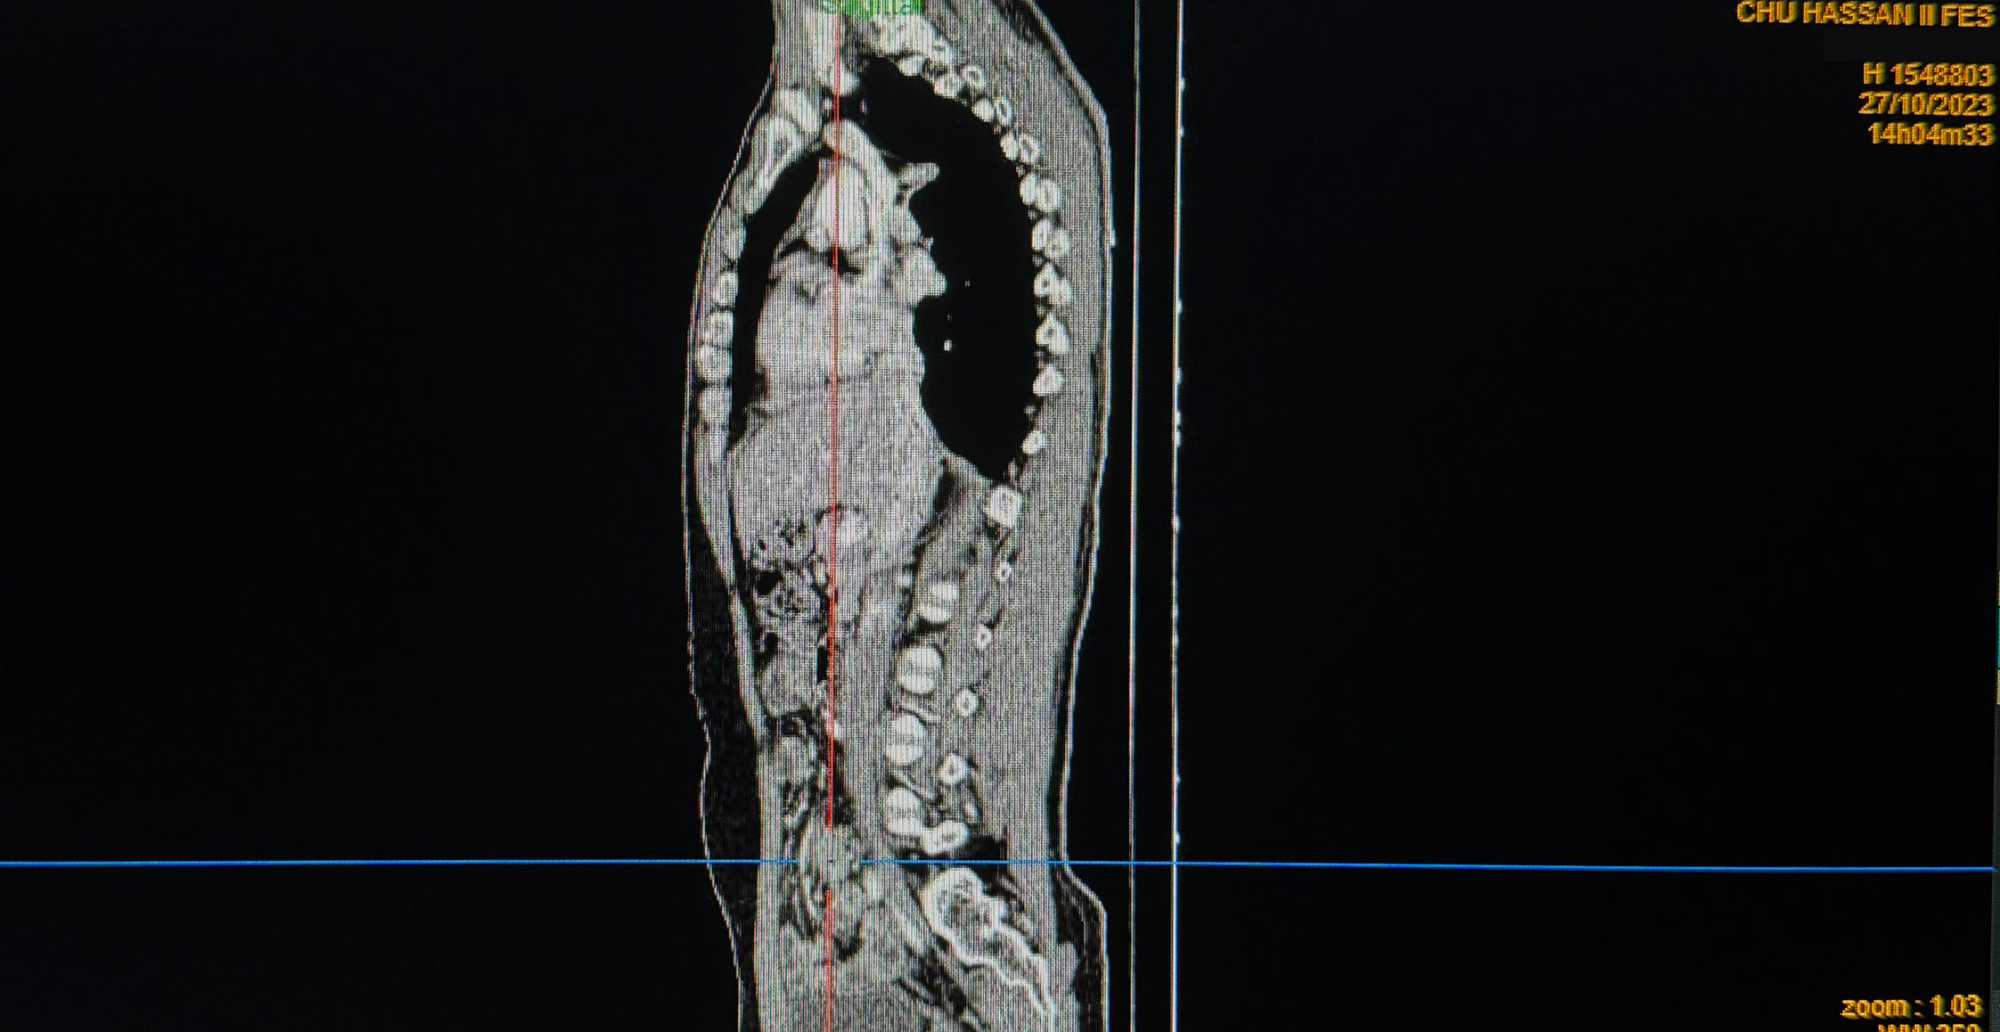

A reassessment CT scan performed on October 27, 2023 (Figures 1-4), after a year of treatment, showed partial regression of the tumor mass measuring then 30 × 18 × 34 mm.

Figure 3. Partial tumor regression on parasagittal CT after 12 months of sorafenib treatment.